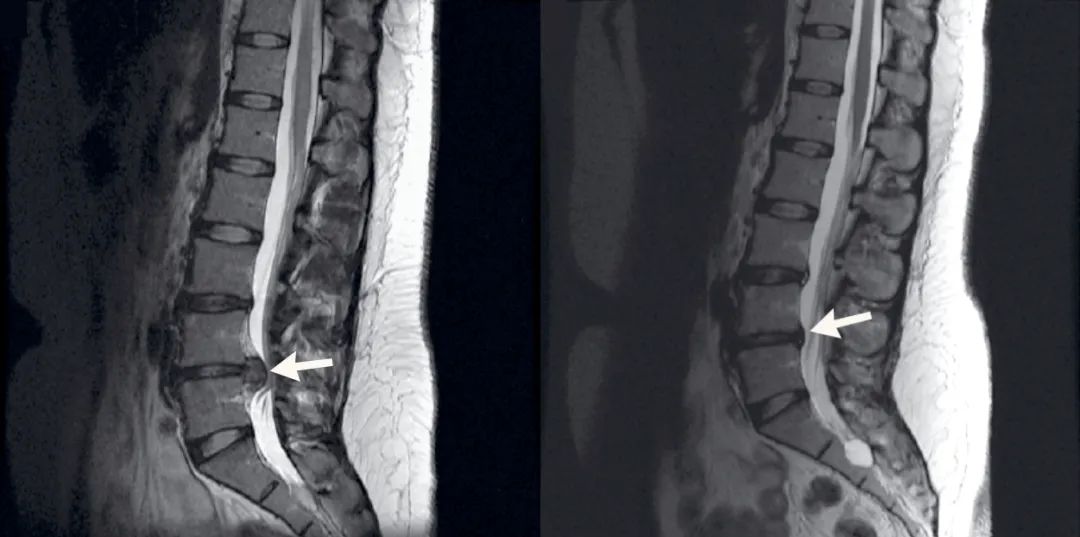

图二:LDH 患者 L4/5 发生自发性消退,MRI 显示 3 年后在 L5/S1 上出现新的突出。图源:DOI: 10.1155/2016/1538072